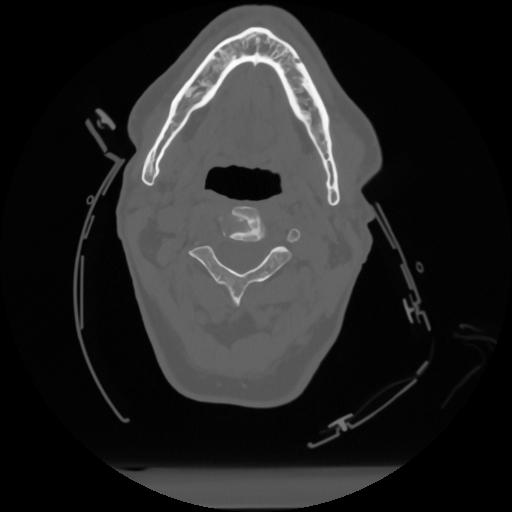

12 P.BLANDAS,,Vol,0.5,P.BLANDAS,,